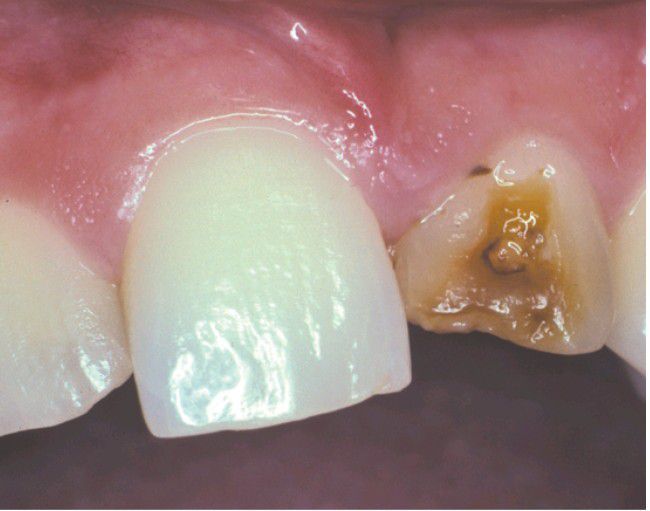

Turner's hypoplasia

Extensive coronal hypoplasia of permanent maxillary left central incisor secondary to previous trauma to deciduous central incisor.